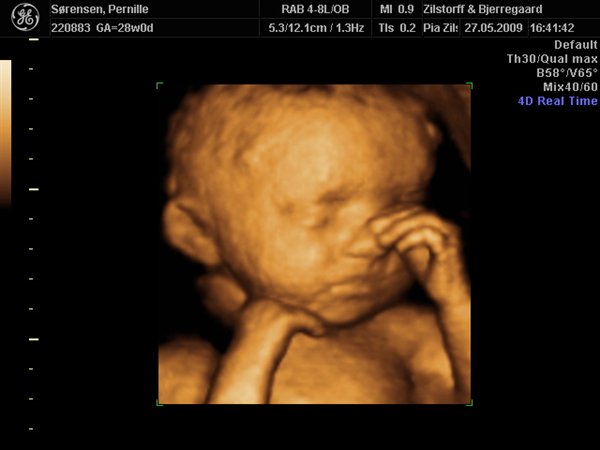

Det jeg har fået af vide er at jeg er i risiko for at føde for tidligt og derfor er jeg under observation og går til kontrolskanning og lægesamtaler hver 14. dag.

Der er vidst også risiko for at lillepigen får svært ved at sætte sig fast med hovedet og så kan jeg ende i kejsersnit.

De troede i første omgang at det skyldte sukkersyge, men det har jeg da (heldigvis) fået udelukket. Sidsta gang fik jeg taget en masse blodprøver for at tjekke for infektioner - hvis det heller ikke er årsagen, ja så ved de det vidst ikke!